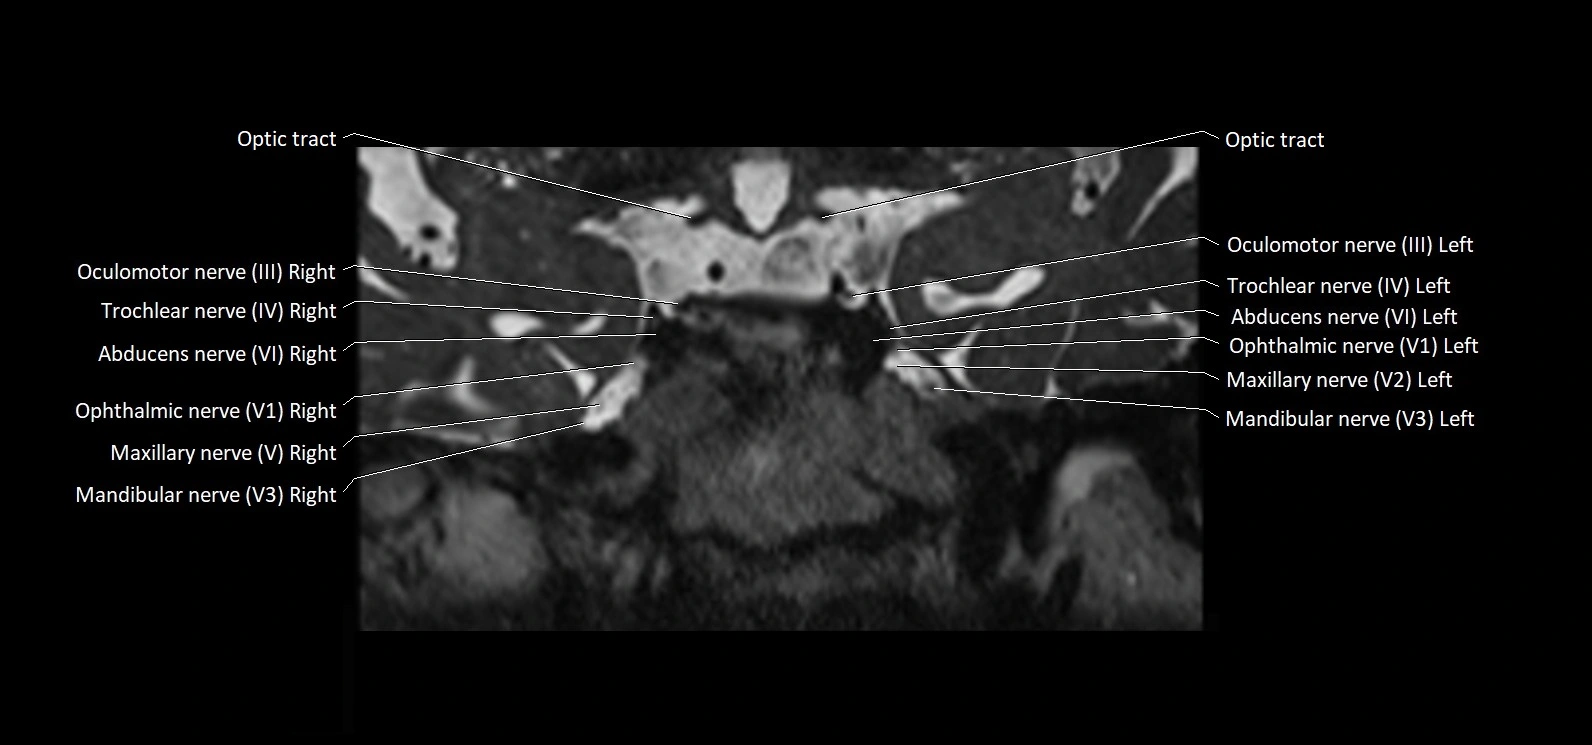

MRI Appearance

• The abducens nerve is a small, thin, linear structure

• Best visualized on high-resolution T2-weighted 3D MRI sequences (e.g., FIESTA or CISS)

• Seen as a hypointense (dark) line running from the brainstem at the pontomedullary junction, traversing the prepontine cistern, and entering Dorello’s canal under the petrosphenoidal ligament, then into the cavernous sinus, and finally the orbit

• May be challenging to visualize in standard MRI due to its small size

• Pathology may be inferred by absence, displacement, or enhancement of the nerve

MRI images

image